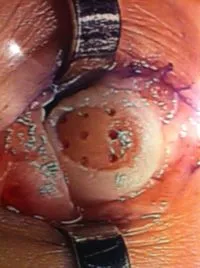

Pics of nodules removed during scope.  A separate incision had to be made to remove the nodules due to the size.